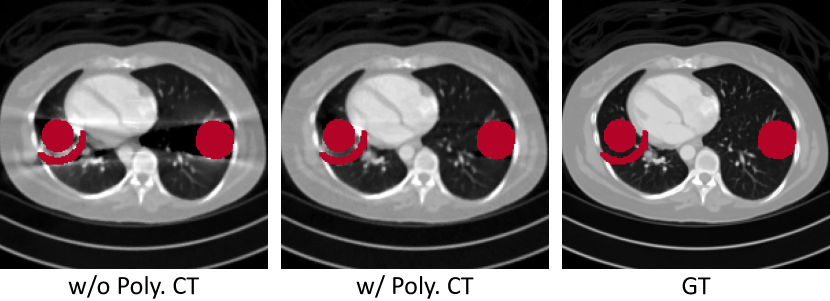

Refer to caption

Figure 4: Qualitative results of our Polyner ablating the polychromatic CT forward model on a sample (##\#6) of the DeepLesion dataset [43]. The red regions denote metals.

Table 2: Quantitative results of our Polyner ablating the polychromatic CT forward model on the DeepLesion dataset [43].

Module PSNR

w/o Poly. CT 32.95±plus-or-minus\pm4.31

w/ Poly. CT 36.87±plus-or-minus\pm1.56

Influence of Polychromatic CT Forward Model. We explore the efficiency of the polychromatic CT forward model in our Polyner. To this end, we replace it with the linear integral transformation as in [21, 22, 23, 24, 25, 26]. Other model configurations are kept the same for a fair comparison. Fig. 4 demonstrates the qualitative results. From the visualization, it is clear that without the forward model, our Polyner almost fails to handle the shadow artifacts caused by the nonlinear metal effect. In comparison, our full model with the forward model produces a clean CT image that is very close to the GT image. We present the quantitative results in Table 2. The results indicate that it contributes to an essential improvement of +3.92 dB in PSNR.